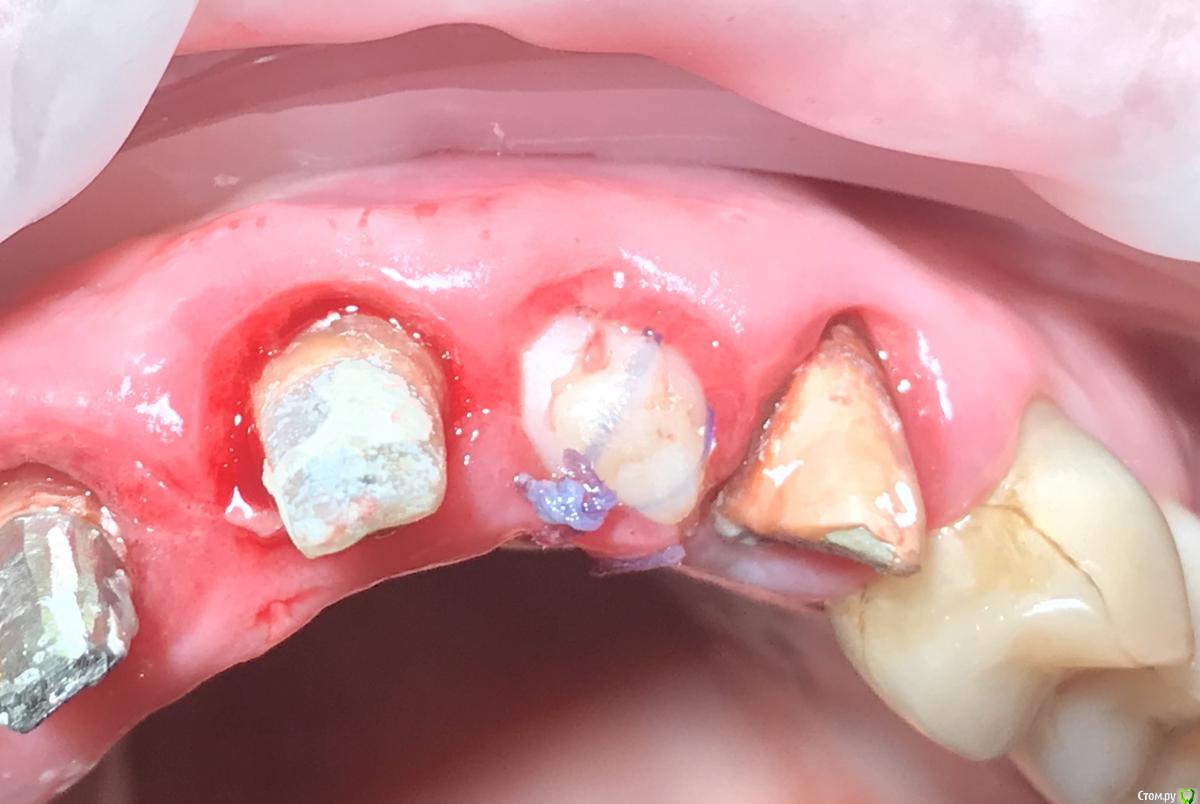

колесников Опубликовано 10 мая, 2019 Поделиться Опубликовано 10 мая, 2019 Удаление с консервацией под мост,закрыто быстрымноймаером. Вид через 3 недели . Удаление повязки,под ней не созревший гранулят,замена на овоид. Следующий визит через месяц,посмотрим будет ли стабилен десневой контур. 3 Ссылка на комментарий